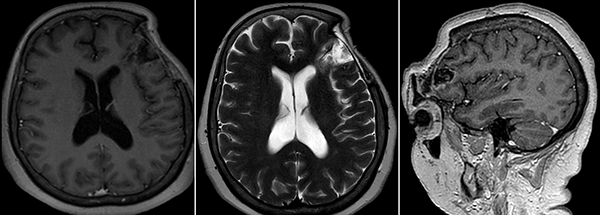

Figura 6.

RM de cerebro control a los 4 meses postoperatorio.